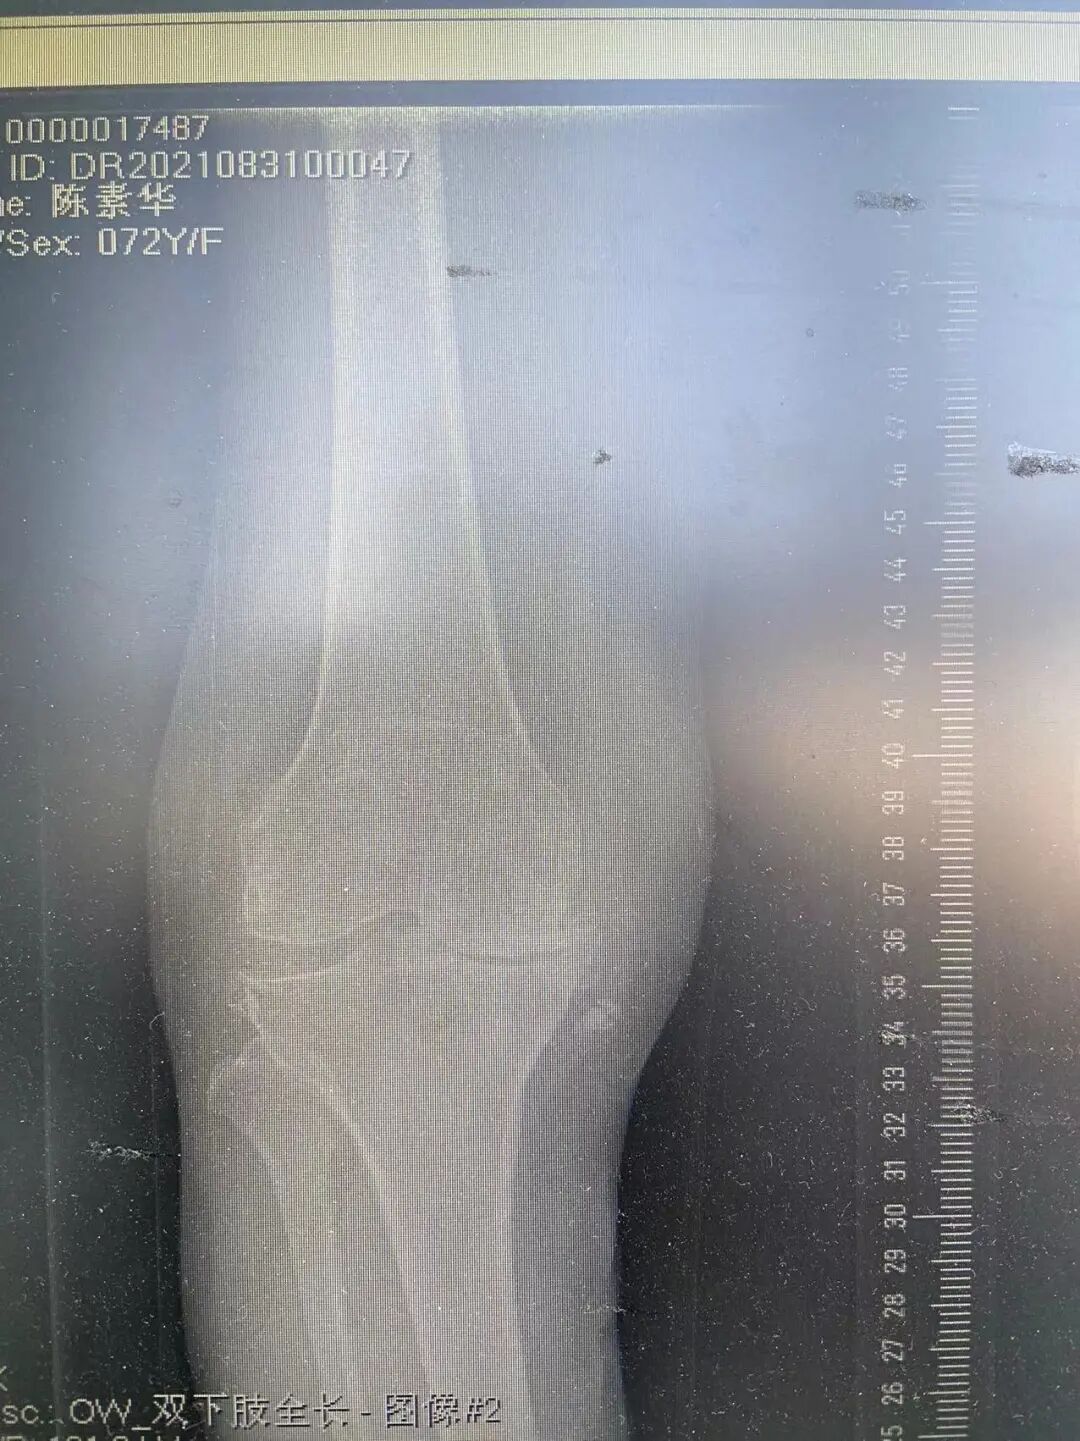

右膝重度骨关节炎

右膝全膝置换术